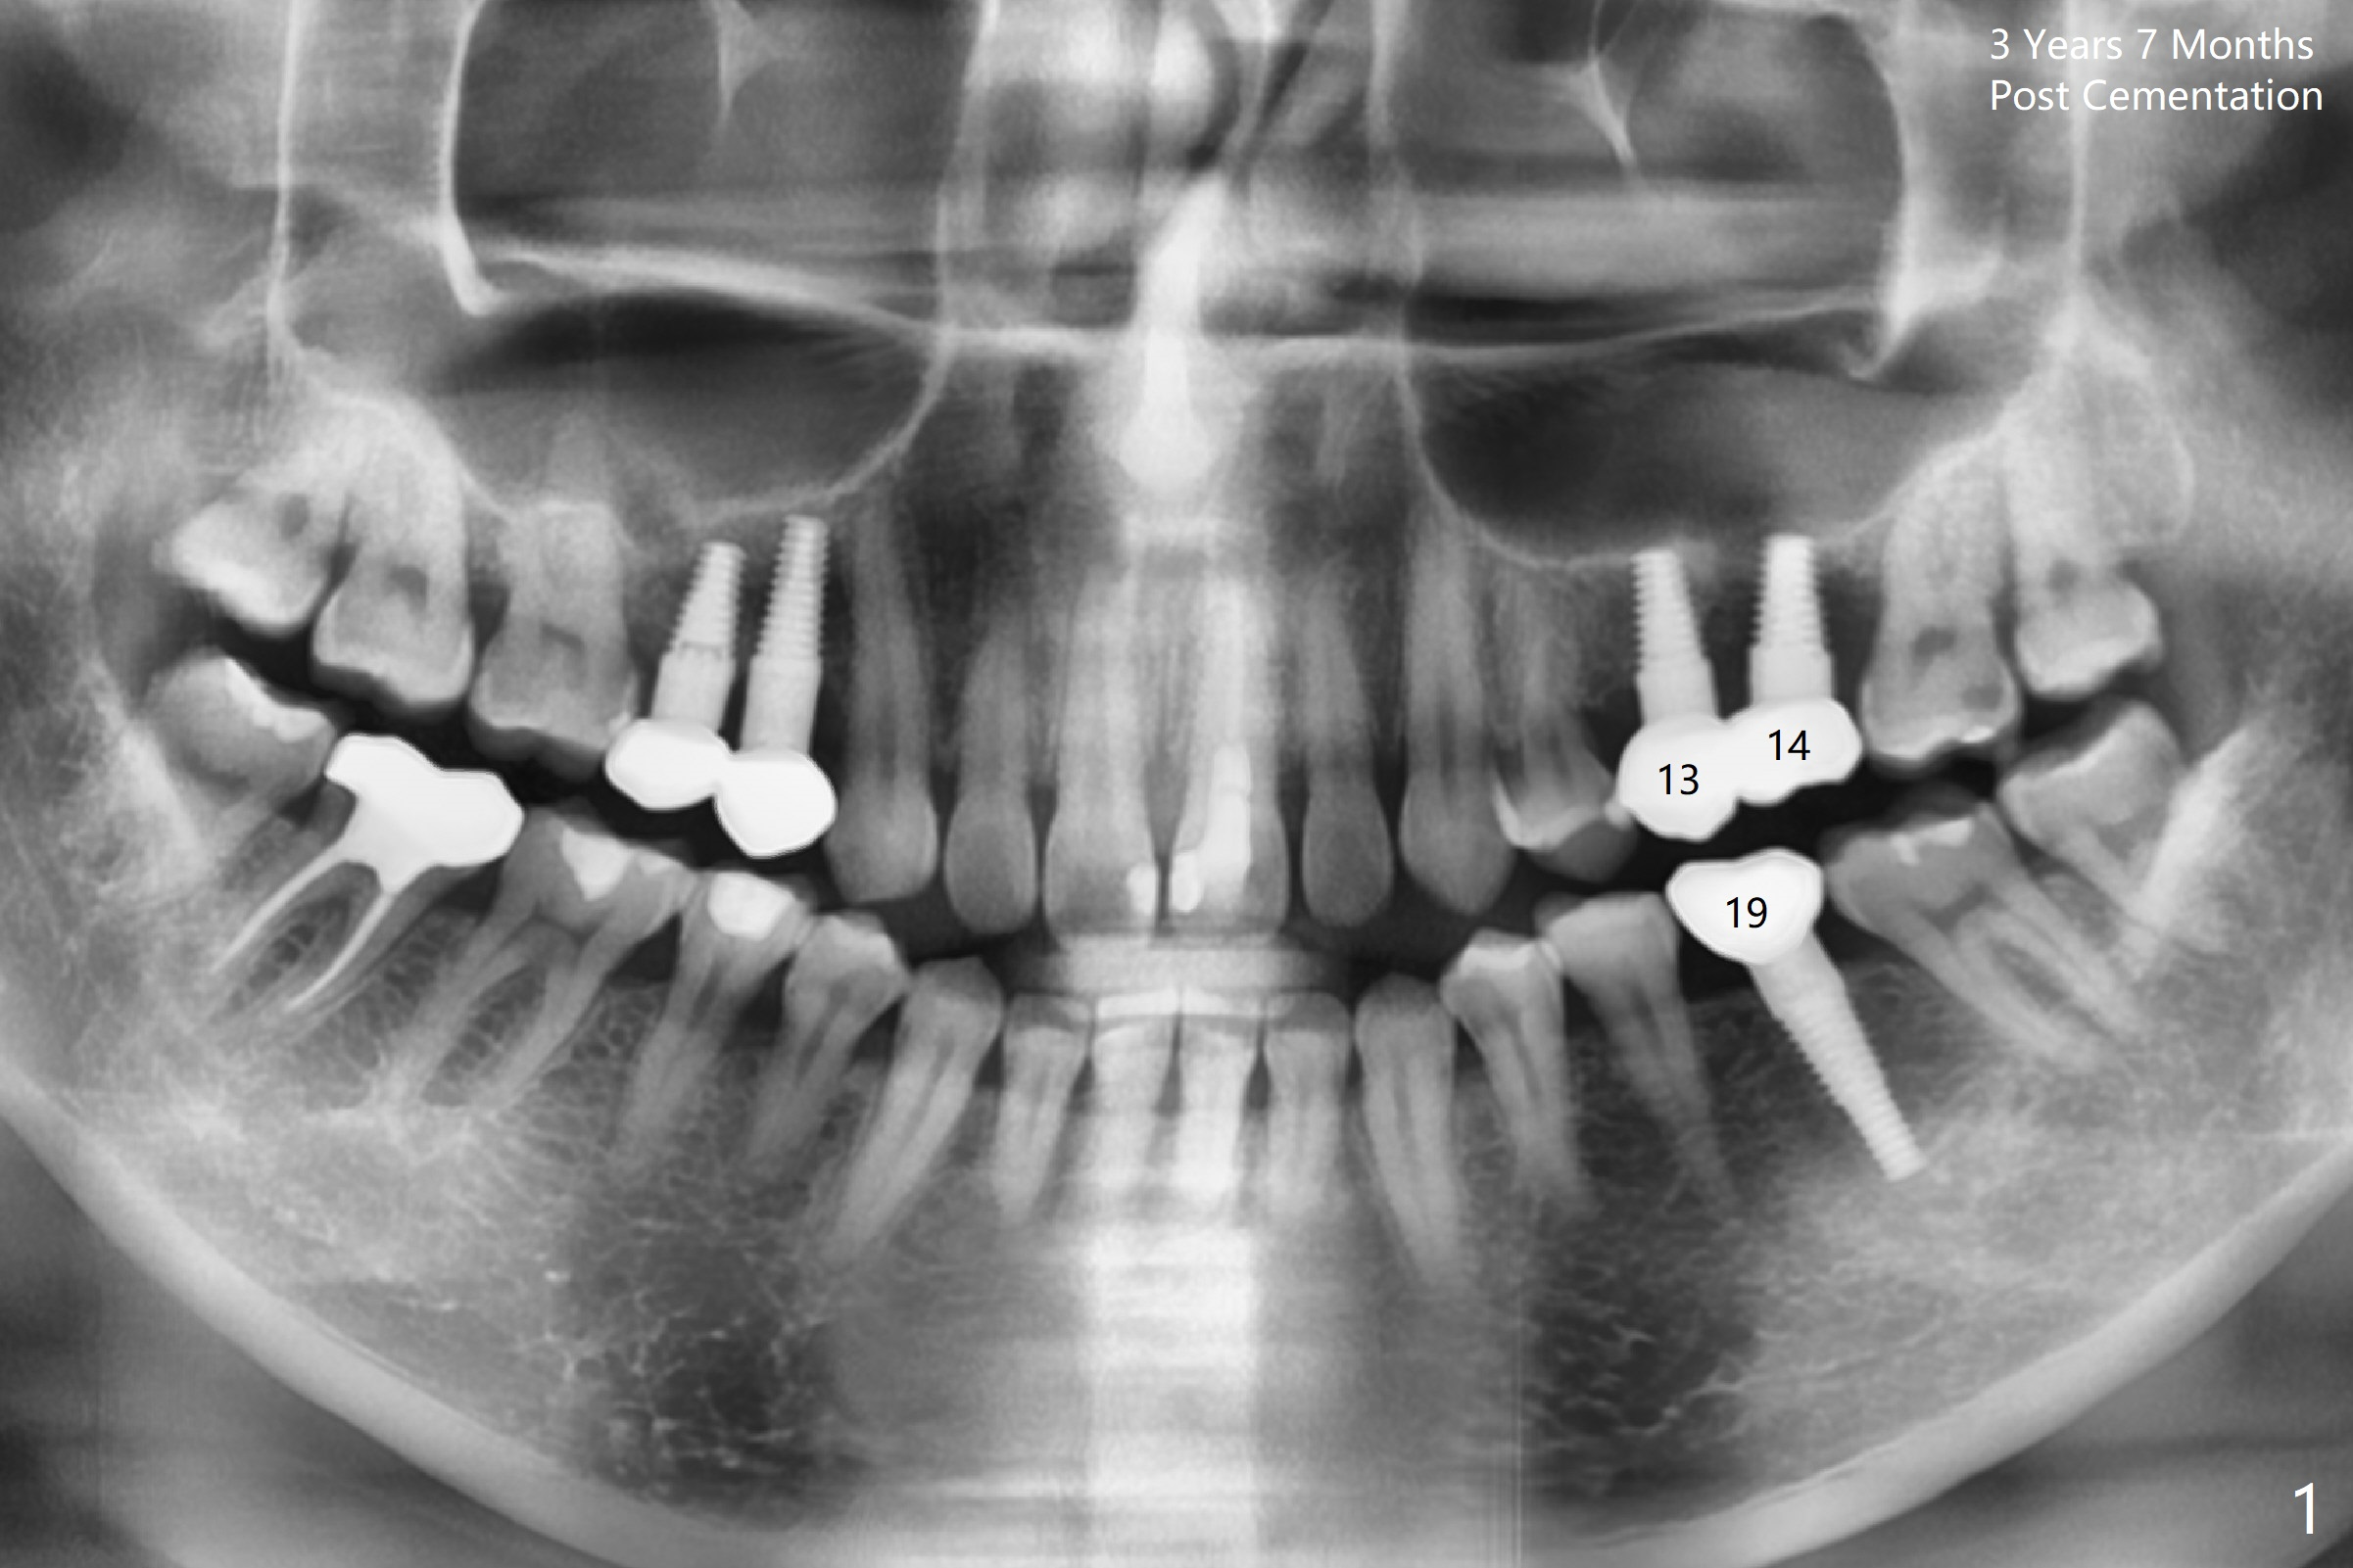

A 32-year-old woman develops periimplantitis (severe hemorrhage and deep pockets) at #14 three years 7 months post cementation (Fig.1).  A 4.5x11 mm implant is placed with flap at #13 after failure for the 1st time (Fig.2), while a 5x11 mm implant is placed flapless with sinus membrane perforation.  Uniposts are cemented with Ketac.  The lingual plate at #14 is defective (Fig.3).  The implant at #14 will be removed flapless, followed by Osteogen plug (most likely sinus floor defect) and bone graft.  After healing, an implant will be placed with guide.  By breaking the proximal contacts, the crown, abutment and implant at #14 are shaken loose using forceps.  Finally the crown breaks off.  Make a slot on the top of the abutment and use a screw bit to turn the abutment/implant counterclockwise.  There is abundant granulation tissue with arterial hemorrhage associated with granulation tissue removal.  The defect involves the distal surface of the implant at #13 and the mesial surface of the tooth #15.  Therefore bone graft is deposited in these surfaces (Fig.4 arrowheads, as compared to preop BW, Fig.4').  The periodontal dressing seems to remain in place asymptomatic 7 days postop (Fig.5).  The bone height 5.5 months postop should be enough for implantation (Fig.6).  To avoid marker associated with guided surgery, free hand will be adopted.  Sinus lift with PRF is expected.  To place in the middle of the ridge buccopalatally, incision will be made with bone expansion.